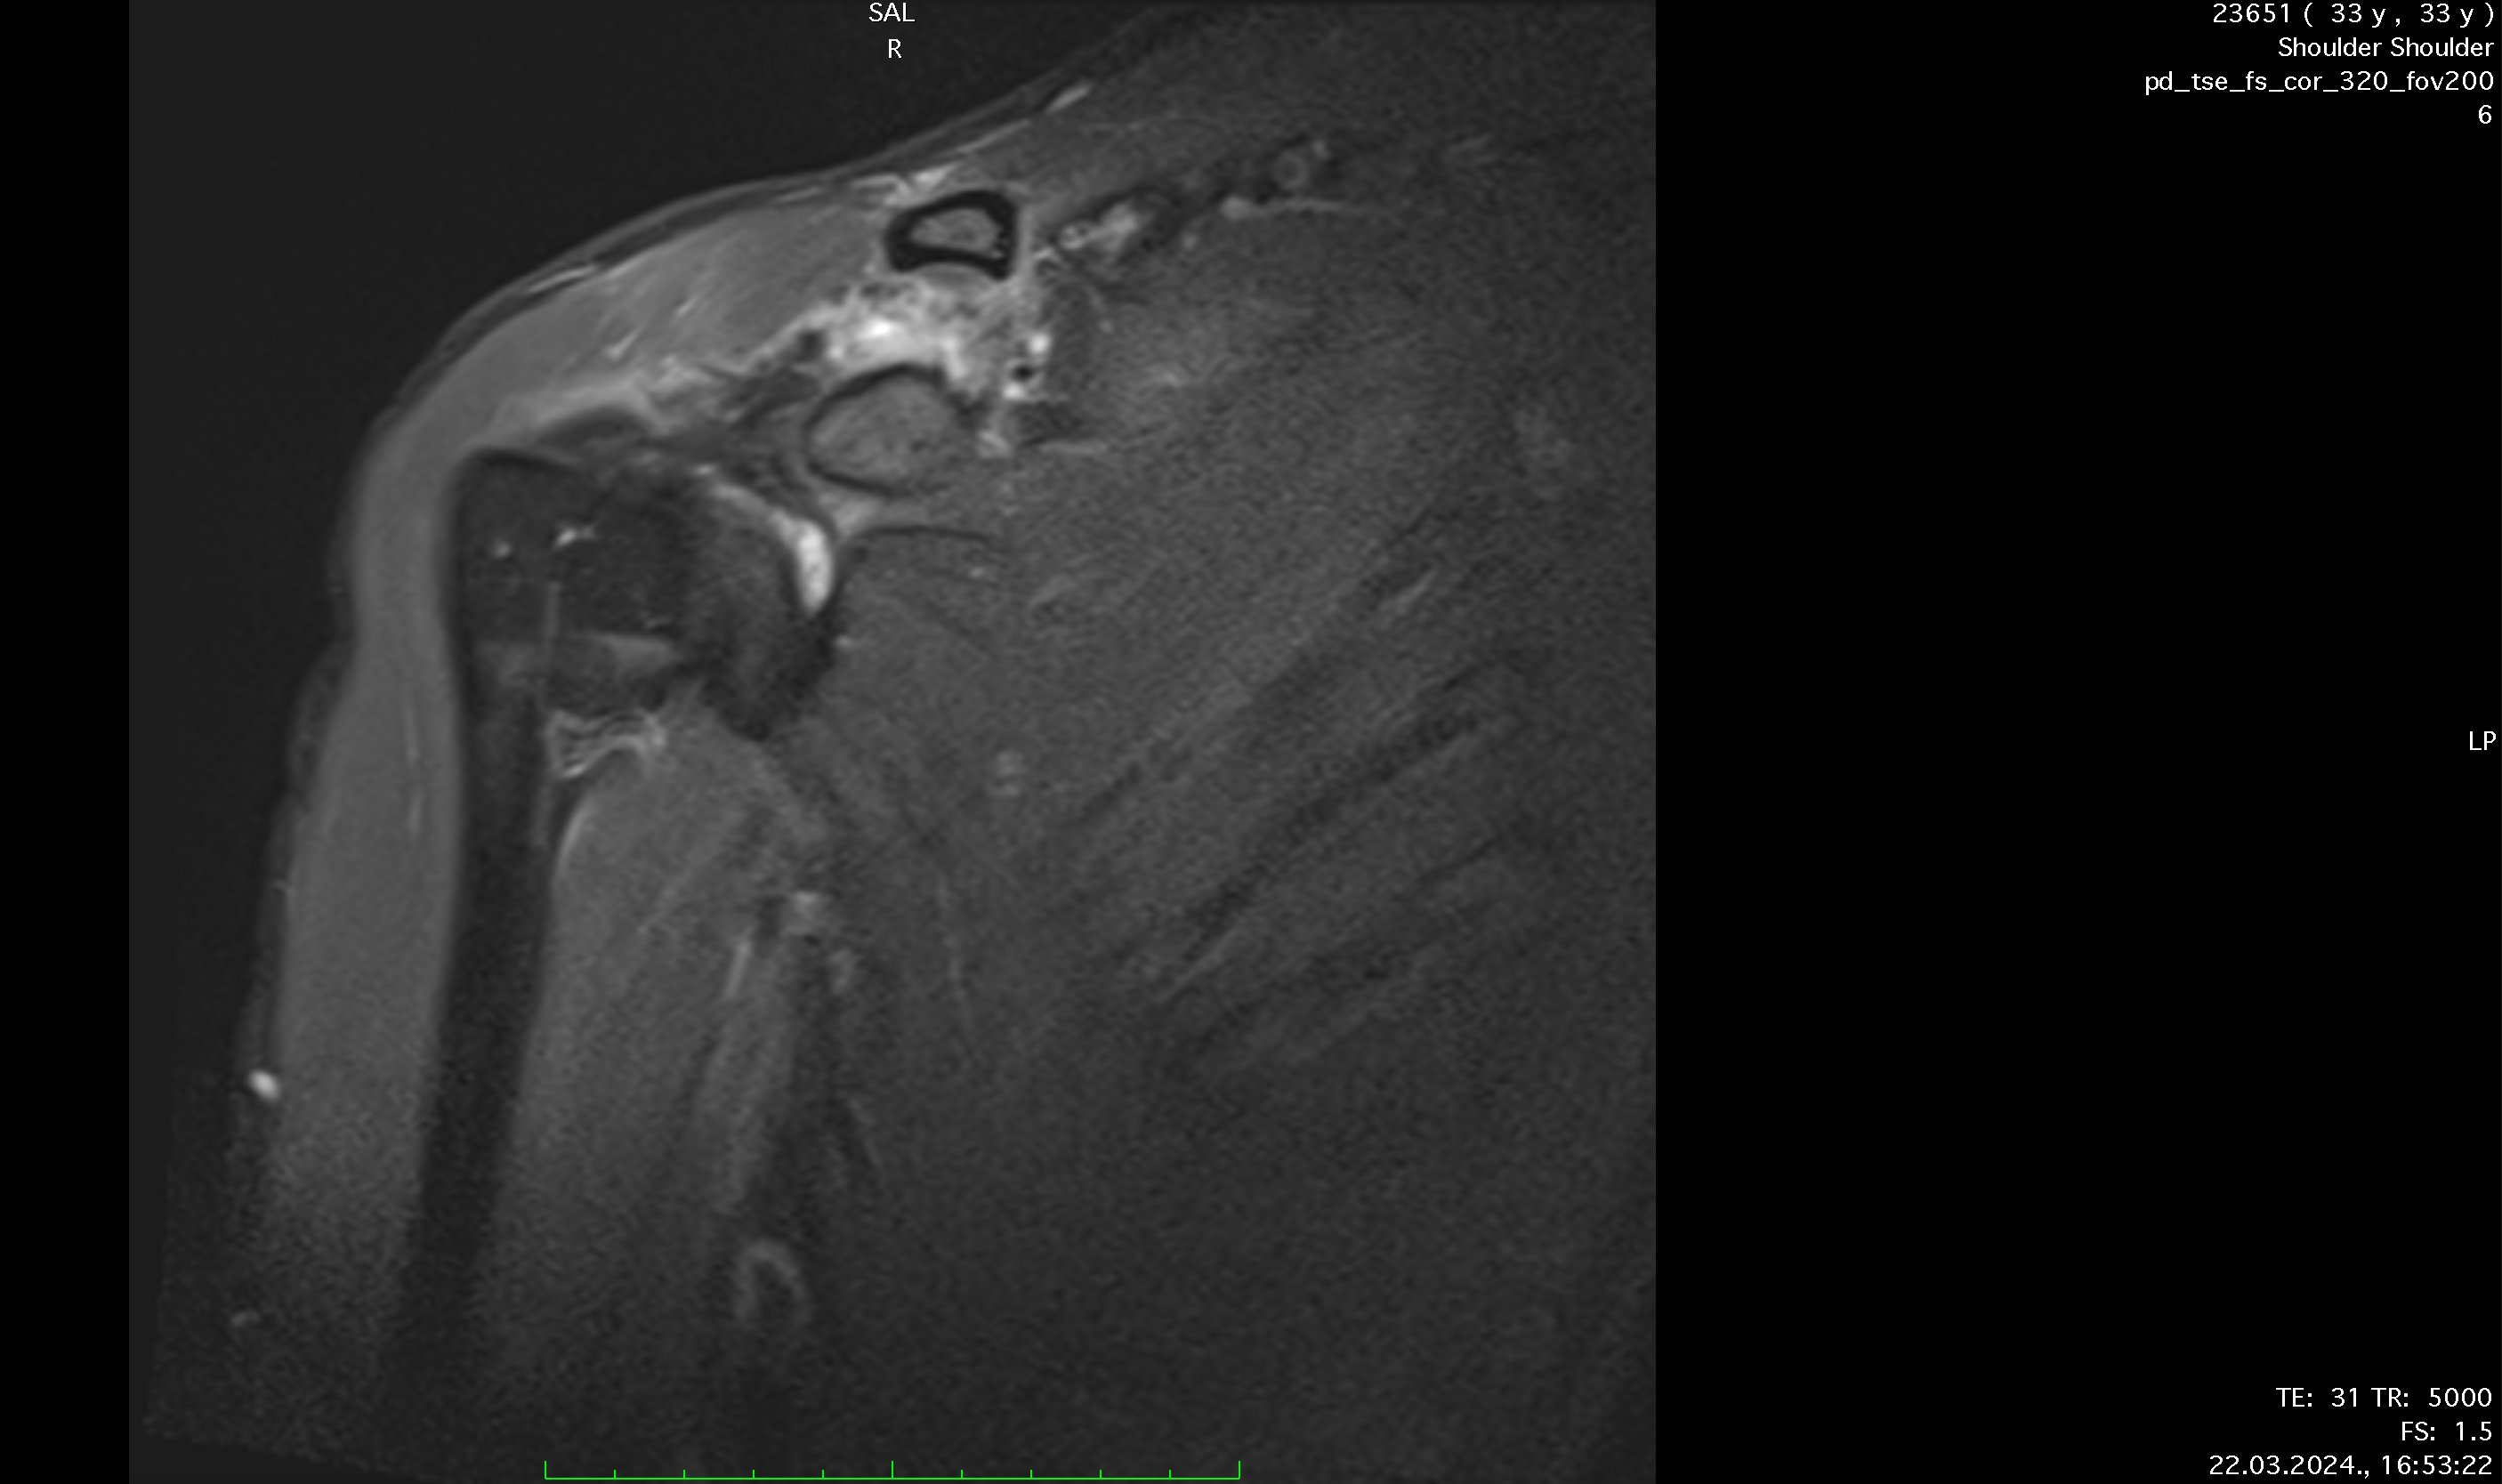

Ten days after the injury, the player's pain level had decreased to 3 out of 10, and nearly full ROM had been regained. A follow-up MRI showed significant recovery, with the AC joint fully reconnected and healed ligaments, though there was some residual edema caused by inflammation from the prolotherapy. Treatment continued for another week, during which the player engaged in more active exercises, including mobility, weight-bearing, and rotator cuff strengthening. While fast movements initially caused stiffness, this resolved within 3 to 4 days.

Reconnection of coracoclavicular ligament, soft tissue, trapezius m., regeneration, formation of AC joint capsule visible after only 8 days of therapy.